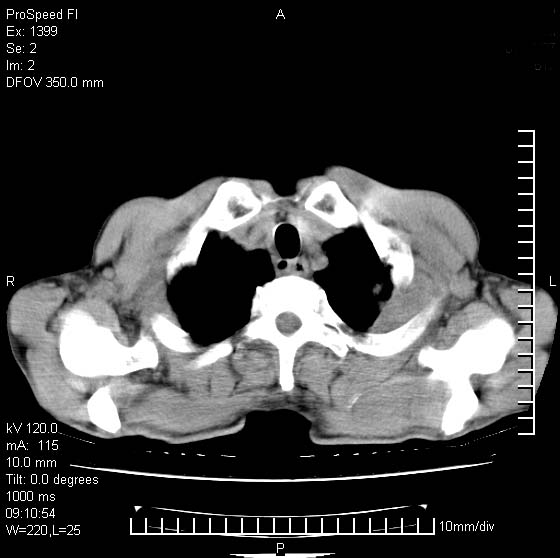

以下是引用卜一在2007-1-19 9:55:00的发言:[br]左肺沿胸膜下巨大肿块影,边缘呈分叶征,纵隔内见肿大淋巴结,右肺内另见一不规则结节影 .考虑:左肺周围性肺癌伴纵隔 右肺内转移.

以下是引用rgsyyf在2007-1-19 11:05:00的发言:[br]左肺上叶见形态不规则巨大软组织肿块影,边缘呈分叶征,纵隔内隆突下见肿大淋巴结,右肺内另见一不规则结节影 .考虑:左肺周围性肺癌伴纵隔即右肺内转移.